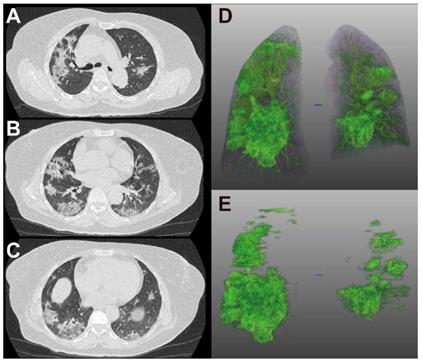

Figure 4 and 5 showed two typical cases with and without clinical endpoint during hospitalization.

Figure 4

65-year-old woman with coronavirus disease 2019. A-C. Non-contrast CT was performed on day of admission. D. Three-dimensional volume-rendered reconstruction shows the distribution of the opacities. E. Pulmonary opacities segmented by AI system. The patient had history of diabetes and hypertension and showed fever at admission. Patient developed acute respiratory failure at the third day of hospitalization. Lung CT images showed large areas of bilateral consolidation and ground-glass opacities, specifically in the upper lungs.

Theranostics Image